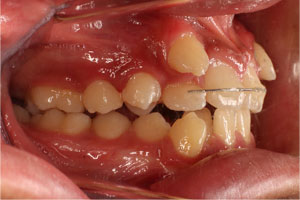

こちらの初診(男性)の患者さんは、開咬合 / 叢生歯列の症状がありました。

1期治療 8歳9ヶ月 2期治療 12歳4ヶ月から治療を開始し、1期治療 7ヶ月 2期治療 2年5ヶ月の間、スタンダードエッジワイズ法(与五沢エッジワイズシステム)を用い矯正治療を行いました。

| 治療開始年齢 | 1期治療 8歳9ヶ月 2期治療 12歳4ヶ月 | |||||||||||||||||||||||||||||||||||||||||||||||||||||||||||

| 症例分類 | 開咬合 / 叢生歯列 / 偏位咬合 | |||||||||||||||||||||||||||||||||||||||||||||||||||||||||||

| 8歳9ヶ月 | 9歳8ヶ月 | |